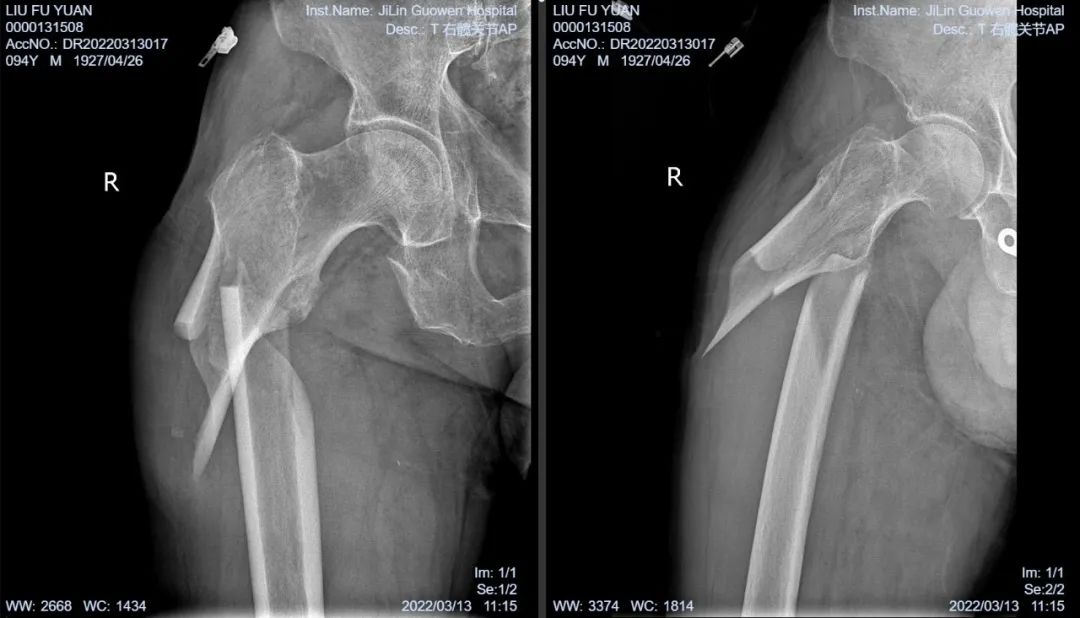

3月13日伴著急促的腳步聲、轆轆的車輪聲,夾雜著患者痛苦的呻吟聲,一位94歲的高齡老人被急診科醫(yī)護(hù)人員緊急送至骨科療區(qū)。這是怎么回事?呂國褔主任帶著值班醫(yī)生在做好防護(hù)措施后,第一時間來到患者病床前,經(jīng)急診科醫(yī)生診斷告知為 “股骨近端粉碎性骨折”,患者右大腿近端嚴(yán)重畸形,骨折端已經(jīng)刺穿前方肌肉直達(dá)皮下,局部皮膚高高隆起,局部皮膚有挫傷灶,呈青紫色,皮膚變薄,皮膚外可明顯觸及骨折斷端,右股骨X線片示:右股骨近端粉碎性骨折,斷端移位明顯,斷端銳利,近斷端位于前方皮膚下,局部皮膚隆起。患者疼痛劇烈,痛苦難耐,測生命體征:血壓:220/110mmHg。